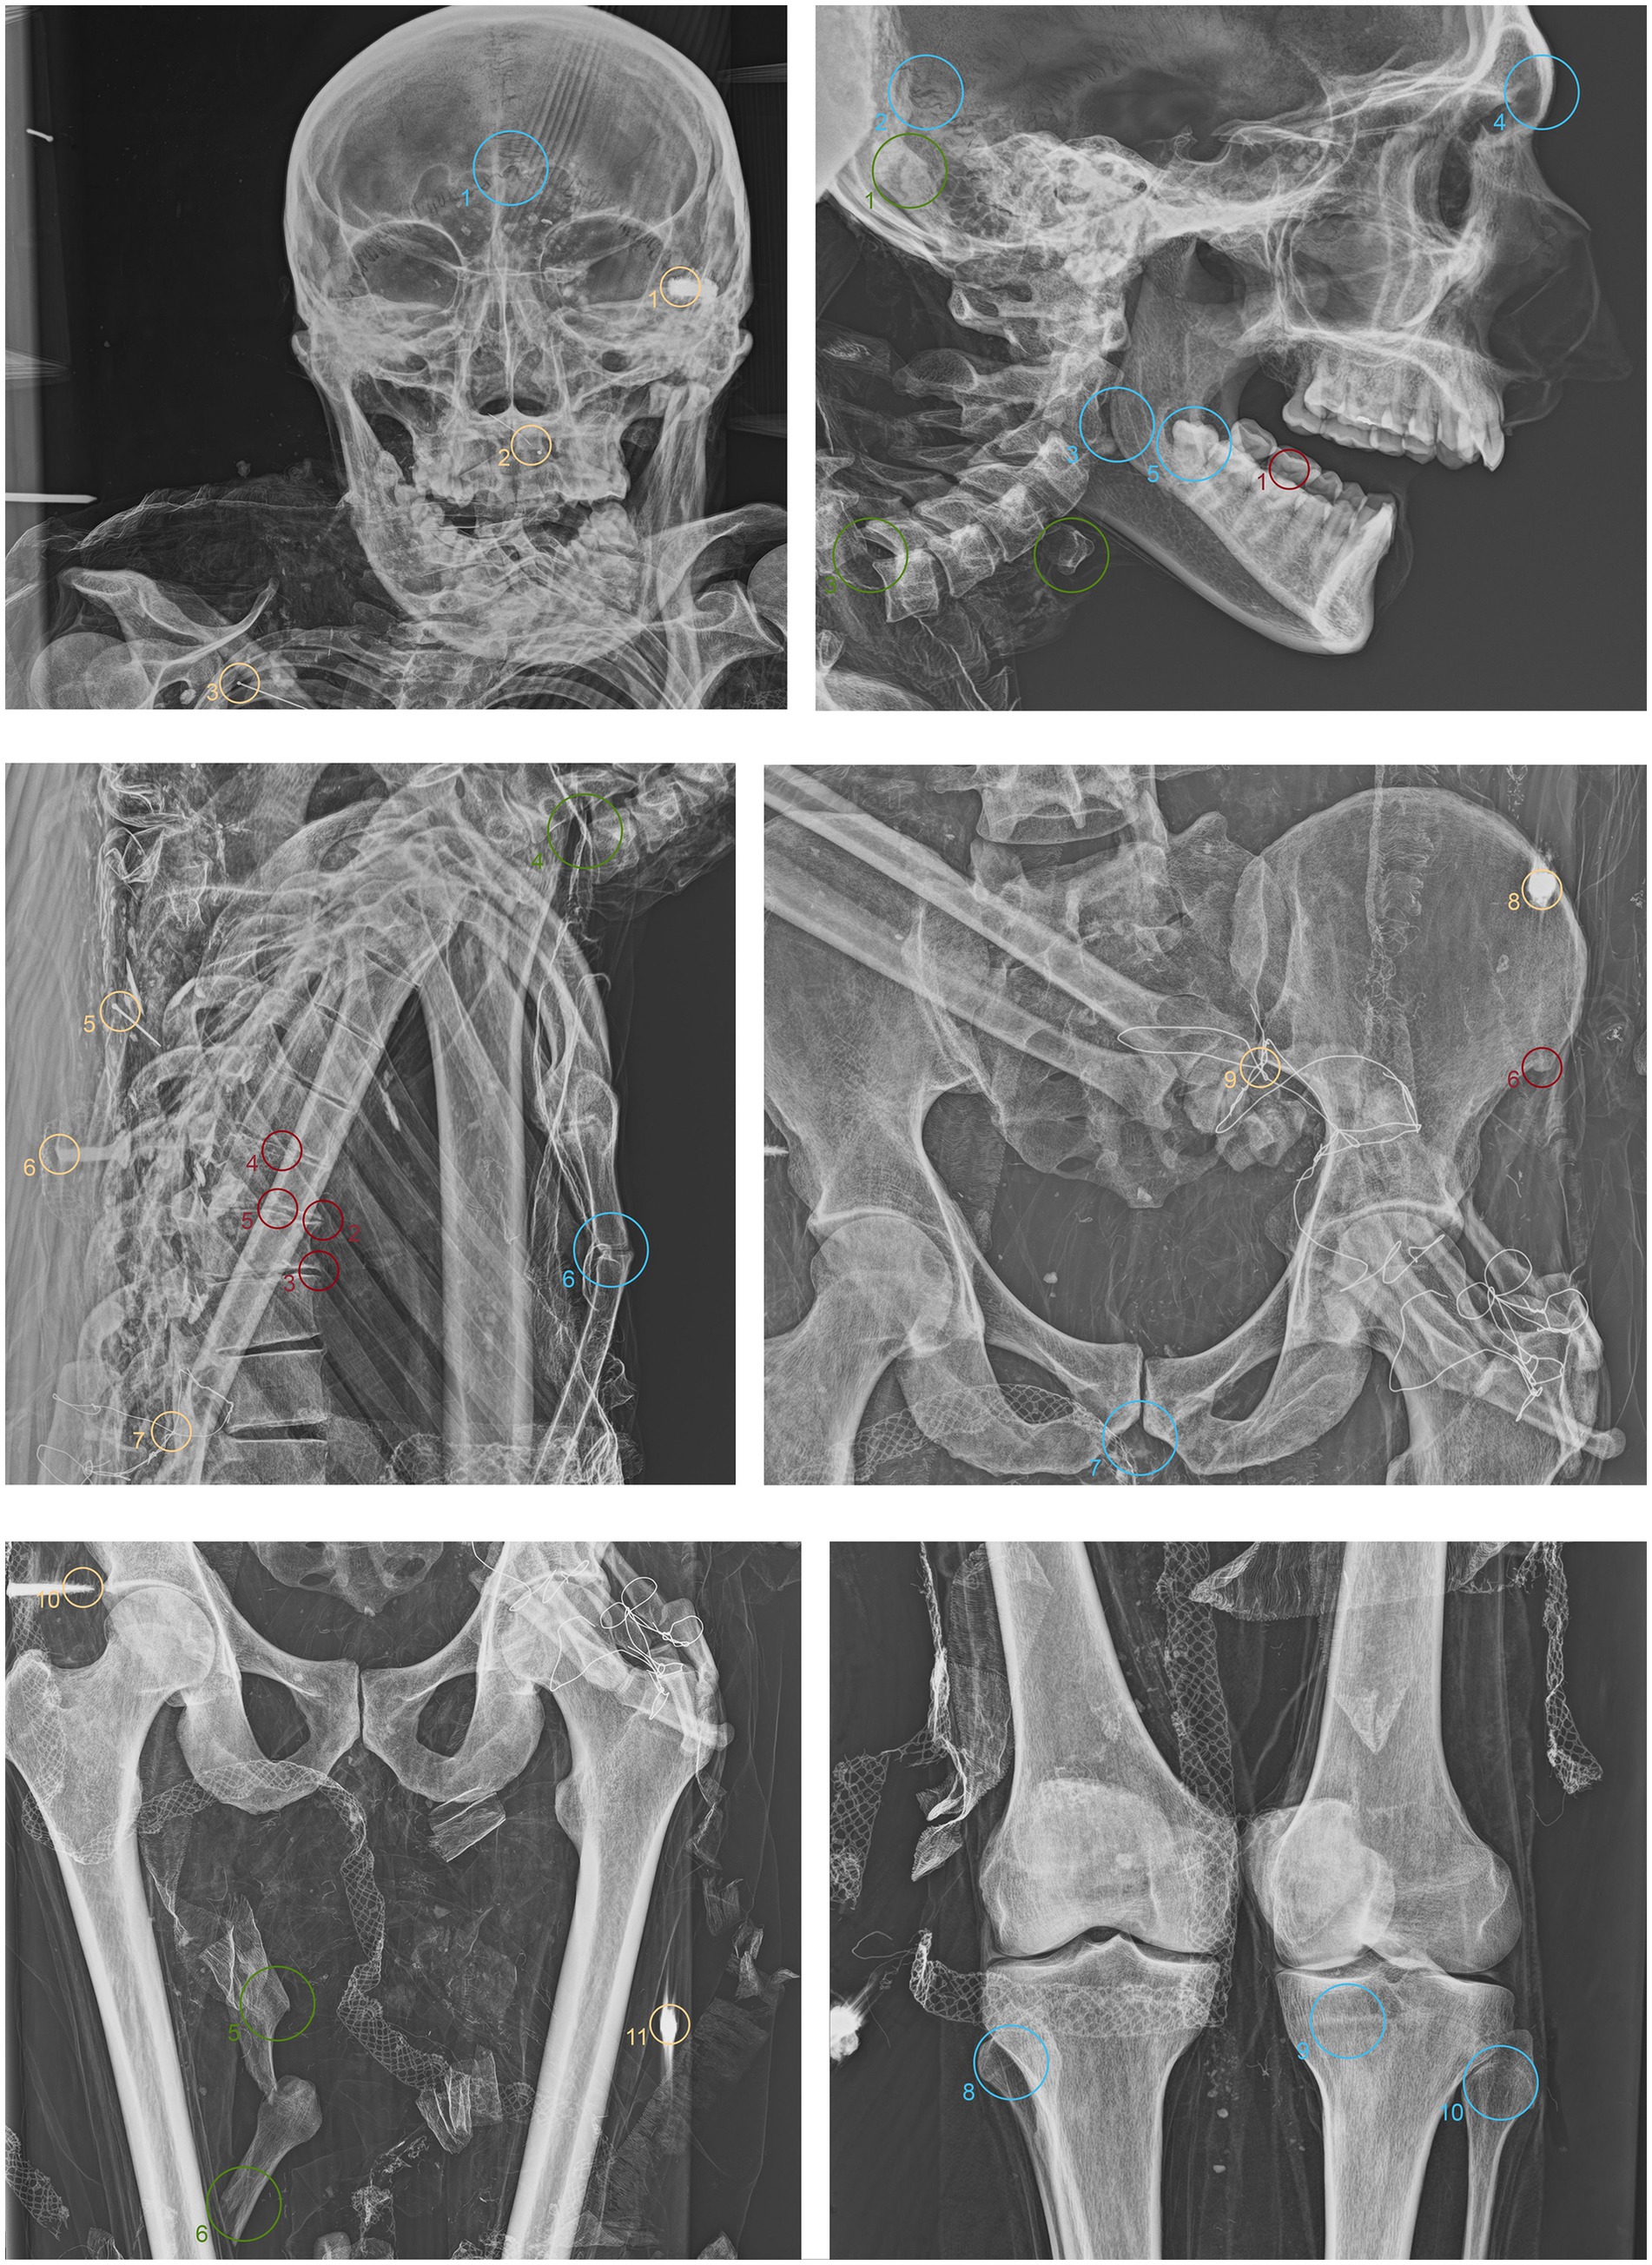

ID2. In this subject, fine material is detectable in the occipital region, forming a single layer parallel to the mummy’s deposition axis (Figure 5.1 green). The cervical vertebrae and the first thoracic vertebra are no longer in anatomical connection, disrupting the continuity of the spinal column (Figure 5.2 green). They have migrated beneath the right side of the thorax at the mid-thoracic level, extending down to the lumbar region (Figure 5.5,6,10 green). Additionally, some teeth are not in an anatomical position—one within the thoracic cavity and another in the pelvic area (Figure 5.3,4,7,11 green). The sternum has migrated to the lower right thoracic area, and a medial phalanx is also displaced (Figure 5.8,12 green). The left clavicle is more vertical compared to the contralateral side, and, in addition, there is a slight retraction of the arm and forearm (Figure 5.9 green). The sacroiliac articular surface is particularly prominent, as is the pubic symphysis, exposed due to the separation of the two halves (Figure 5.13; Figure 6.1 green). The right femur is also rotated laterally by about 90° (Figure 5.14 green), causing lateral rotation of the knee and tibia. Notably, a fold in the soft tissues of the left thigh is evident at the level of the distal diaphysis of the left femur (Figure 6.2–4 green).

Figure 5. Anteroposterior and lateral radiographic acquisitions of the pelvis and upper limb of the individual ID2. Green highlights indicate areas of interest for taphonomic study, yellow highlights indicate areas relevant to the assessment of restorations predating this study, violet is used for entomological analysis, blue for anthropological aspects, and red for paleopathological evidence.

Figure 6. Anteroposterior and lateral radiographic acquisitions of the pelvis and lower limb of individual ID2. Green highlights indicate areas of interest for taphonomic study, yellow highlights indicate areas relevant to the assessment of restorations predating this study, violet is used for entomological analysis, blue for anthropological aspects, and red for paleopathological evidence.

ID2. Similarly, the metal nails used to assemble the wooden bases housing the bodies are visible (Figure 5.1,7; Figure 6.1,4 yellow). A particularly radiodense rectangular element wraps around the occipital bone beneath the skull (Figure 5.2,3 yellow). As in the previously discussed subject, metal wire was used to wrap around the left elbow (Figure 5.4,5 yellow) and to bind and tighten the mummified tissues of the right leg (Figure 6.2,3 yellow).

ID2. In the anteroposterior view, a big gonial eversion and a robust mental symphysis are evident, with a prominent mental protuberance and pronounced mental tubercles (Figure 5.1,2 blue). In the lateral view, the pronounced glabella, robust mastoid processes, and relatively open mandibular angle are visible (Figure 5.3–5 blue). The sternocostal surfaces of the ribs show deformities, erosions, and marginal sclerosis (Figure 5.6 blue). Both the lateral and anteroposterior views reveal a narrow sciatic notch (Figure 6.1 blue).

ID2. The skull shows a dense network of venous impressions on the parietal bones, particularly visible in the anteroposterior projection (Figure 5.1,6 red), along with the presence of several Pacchioni’s foramina. The frontal sinuses expand laterally, almost reaching above the orbits (Figure 5.2 red). The anterior nasal spine appears slightly rotated to the right relative to its anatomical axis (Figure 5.3 red). This individual exhibit complete edentulism, associated with mature alveolar bone retracted from the alveolar region (Figure 5.4 red). Proceeding to the analysis of the appendicular skeleton, the acromion of the left clavicle shows marked roughness at the insertion area of the trapezius muscle, as at the origin of the subscapularis muscle (Figure 5.7 red). The joints between the humerus and scapula exhibit greater radiodensity (Figure 5.8 red). An area free of bone overlap allows the observation of increased radiodensity at the insertion of the pectoralis major muscle and inside the humerus-scapular joint (Figure 5.9 red). Heterotopic ossification is also noted on the margin of the lateral border of the scapula (Figure 5.10 red). The thoracic spine presents intervertebral calcification between the 5th and 6th vertebrae (Figure 5.13,16,18,23 red), fusion of the 8th and 9th vertebrae through a dense bony bridge (Figure 5.14,17,19 red), and intense osteophytic change along the margin of the entire segment, particularly evident between the 9th and 11th thoracic vertebrae (Figure 5.11,12,20–22 red). Sclerosis is observed in the superior and inferior vertebral articular surfaces, accompanied by granular and concave areas in the vertebral bodies (Figure 5.15 red). Osteophytes are observed at the insertion points of the oblique muscles on the iliac crest, at the various muscles originating from the ischial tuberosity, and at the insertion area of the iliopsoas muscle during the analysis of the pelvic girdle (Figure 5.24,25; Figure 6.1,2 red). The origin of the gastrocnemius muscle is also particularly pronounced (Figure 6.3 red). At the level of the knee joint, we noticed osteophytes on the margin of the right patella (Figure 6.4,5 red), both on the superior and inferior portions of the joint, as well as on the lateral articular margin of the distal femur and proximal tibia, with productive changes that have significantly altered the morphology of the joint (Figure 6.6,7 red). It is worth mentioning that osteophytes are also present at the insertion of the Achilles’ tendon (Figure 6.8 red).